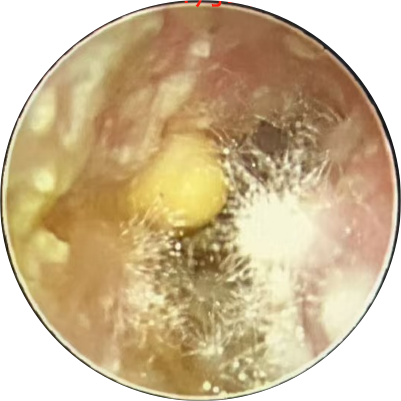

右侧外耳道弥漫性充血,肿胀,潮湿,可见积中等量灰白色分泌物,鼓膜充血,见图1。

图1 2024年10月31日耳内镜